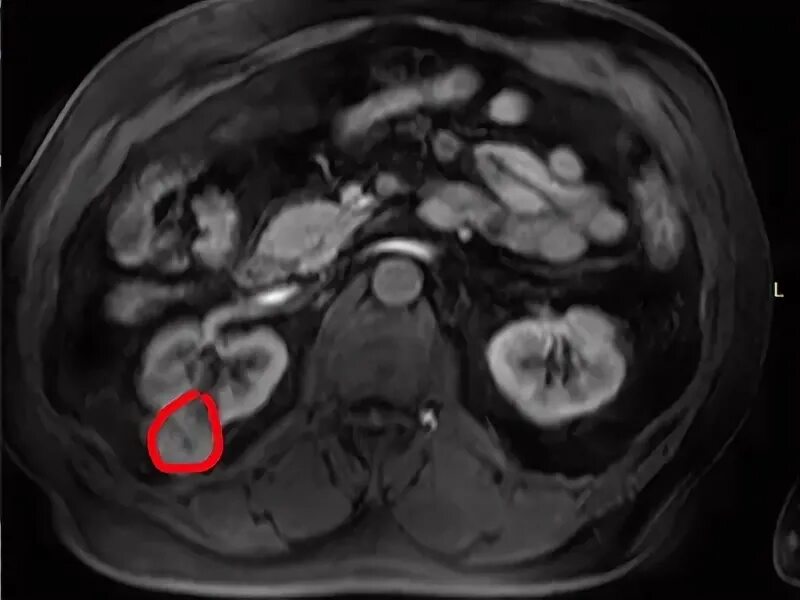

Перед мрт простаты